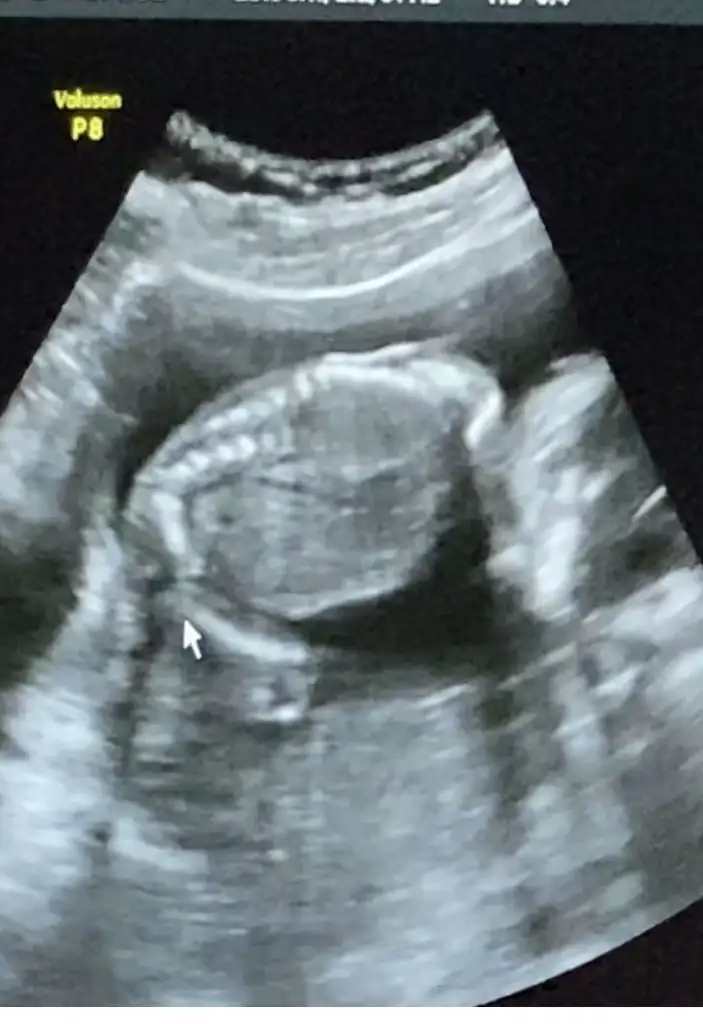

yess ben çıktım✌️😍

evladımızın yüzünü görelim dedik kısmet totosunaymış😂 tam bir troll çıktı🙈🙈

valla videodan foto eklemeye çalıştım ama kusura bakmayın payınıza toto düştü kızlar😂

benden bu kadar ✌️ evladım özlem duyan hepimizin adına yüzüstü yatmış🙈 şimdi sizi totosuyla baş başa bırakıyorum 😂😂